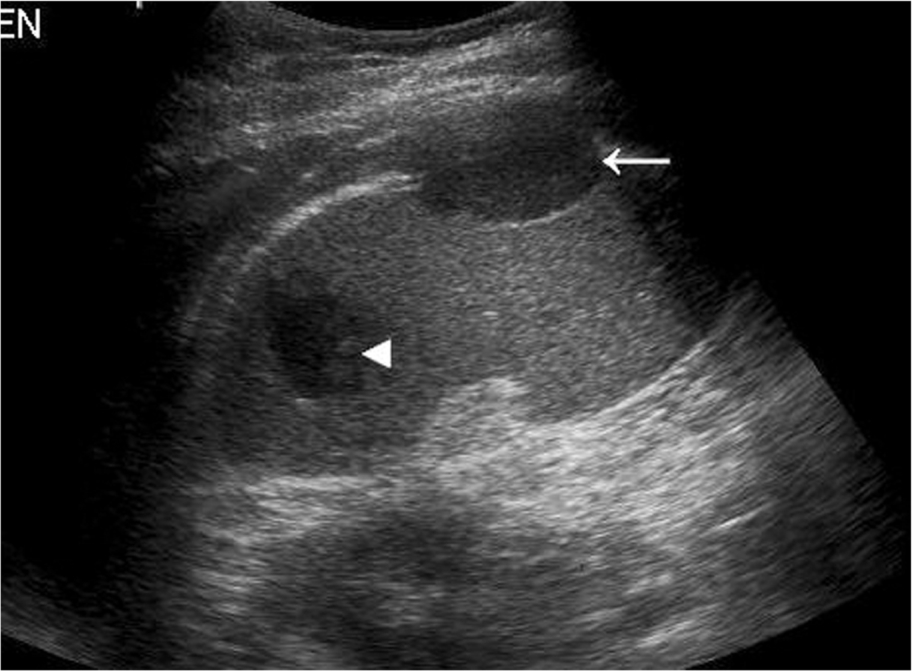

Initially, the area of infarction is hypoechoic and usually wedge-shaped, solitary, and extending to the periphery of the spleen (Fig. 5.7). In the acute phase of infarction, B-mode ultrasound is not often useful, only identifying 50% of infarctions resulting in a high false-negative rate. The lesion may decrease in time and gradually fibrose, becoming hyperechoic. If the infarction is large, it may demonstrate reduced Doppler perfusion when compared to the normal splenic tissue, and CEUS may be particularly helpful in outlining the area of non-perfusion, allowing a definitive diagnosis and is represented as a triangular or slightly rounded area with the base extending to the splenic capsule. In rare cases of total splenic infarction (Fig. 5.7D), because of occlusion of the proximal main splenic artery, gray-scale sonographic appearances may be normal in the early stages.

Pseudoaneurysm in the spleen occurs in a minority of cases following splenic trauma or in the context of chronic pancreatitis. An echo-free or “cystic” area may be observed, which demonstrates flow on color Doppler. To distinguish between a “true” aneurysm and pseudoaneurysm, the following features should be present in a true aneurysm: focal arterial disruption and inflammation at the location of an irregular vessel wall.17